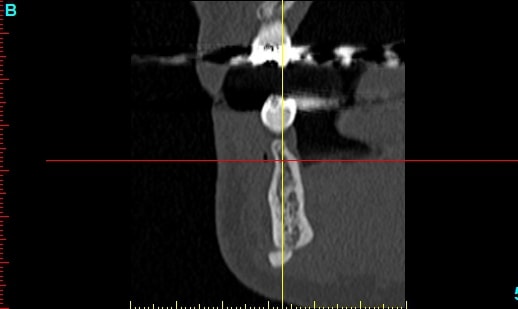

Patiente 58 ans à eu une chirurgie à visée esthétique et "fonctionnelle" adressée pour détartrage en urgence...je ne suis pas spécialiste mais je trouve que la greffe mentonnière est très bof

lésion apicale sur 42 risque de contamination sur la vis en regard..

j'ai demandé un scan en urgence.

Nous sommes d'accord pour la chirurgie mais secteur 4 il y a 2mm être là plastie et la mdble, ça ne me fais pas rêver

La chirurgie à 6 mois

Nous sommes d'accord pour la genioplastie je me suis mal exprimé ce qui m'inquiète c'est la proximité de la greffe, pardon genioplastie et de l'infection de 42, d'une part et la mauvaise liaison de la genioplastie secteur 4, mais je suis peut-être pessimiste.

N'ayant aucune donnée j'essaie d'abord de faire le tri,avant de mettre les mains dedans...je raisonne comme en implanto, quand il y a un foyer infectieux à distance proche (42) je pense qu'il y a un risque...

Plusieurs points: les vis de 15mm x 2mm qui transfixent c'est pas top, une seule plaque, qui plus est non réglable de chaque côté, c'est encore moins top. C'est une plaque de fracture.

En mandibulaire gauche c'est quoi ce fil d'osteosynthese? Un troisième fragment? En laissant l'apex de la 48 pile sur le trait d'osteotomie, je dis chapeau.

Pour la lésion de 42, ca peut être lié à la genio. Forage hasardeux? Mais je vote plus pour une lésion endo/paro